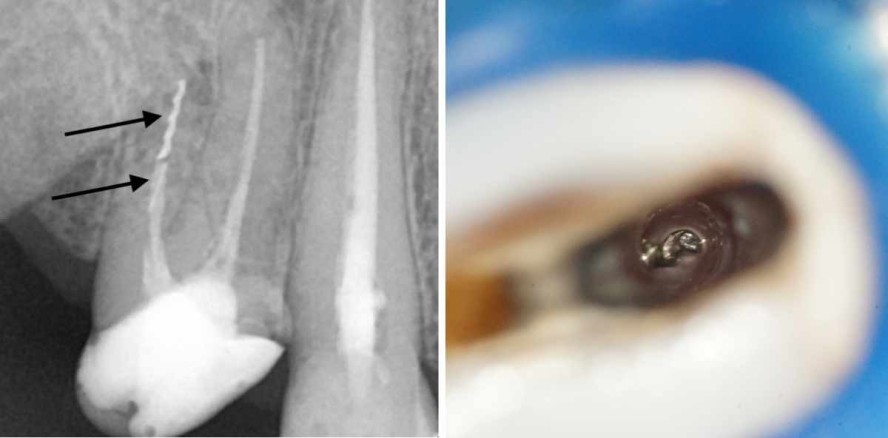

Foto: Dr. Sebastian Riedel

Die mechanische Bearbeitung von Zähnen und insbesondere der Wurzelkanalsysteme beinhaltet das Risiko, kleinere und größere Teile des Instrumentariums darin abzubrechen. Die mechanische Benutzung verschiedener feiner und sehr feiner Werkzeuge führt unverschuldet oder selbst verursacht zum Risiko der Fraktur. In dieser Ausgabe gibt der erste Teil des folgenden Fachartikels einen Überblick über die Thematik frakturierter Instrumente. Im zweiten Teil, der im Endodontie Journal 4/2021 erscheint, werden einzelne praktische Methoden vorgestellt, mit deren Hilfe die effektive und substanzschonende Behandlung von Zähnen mit frakturierten Instrumenten möglich ist.

Verallgemeinernd kann man anmerken, dass sich die meisten Zahnärzte unter einem „Fragment“ ein metallisches Stück eines Wurzelkanalinstrumentes vorstellen, das im Wurzelkanal stecken geblieben ist. In unterschiedlichen Umfragen gaben zwischen 75 und 100 Prozent der befragten Zahnärzte und Spezialisten für Wurzelkanalbehandlung an, schon einmal während der Präparation eines Kanals ein Instrument frakturiert zu haben.1 Neben frakturierten Wurzelkanalinstrumenten gehören aber auch andere Werkstücke zu den im Wurzelkanal auffindbaren Bruchstücken, die während der Behandlung dort verbleiben können:

1. Wo liegt das zu entfernende Fragment? Eine weit koronale Lage im Kanal begünstigt die Möglichkeit der Entfernung gegenüber der tieferen Lage im Kanalsystem.

2. Wie lang ist das Fragment?

3. Aus welchem Material ist das Fragment gefertigt?

4. Welche anatomischen Gegebenheiten beeinflussen die Fragmententfernung positiv oder negativ?